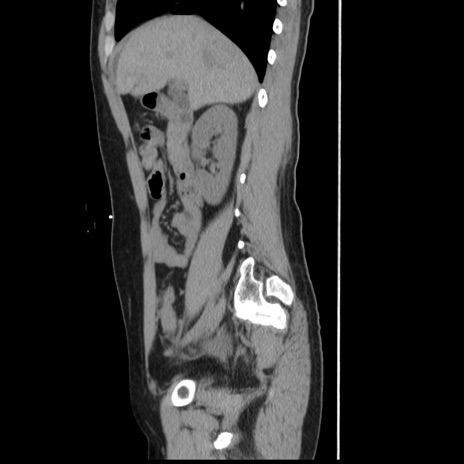

横断像

冠状断像